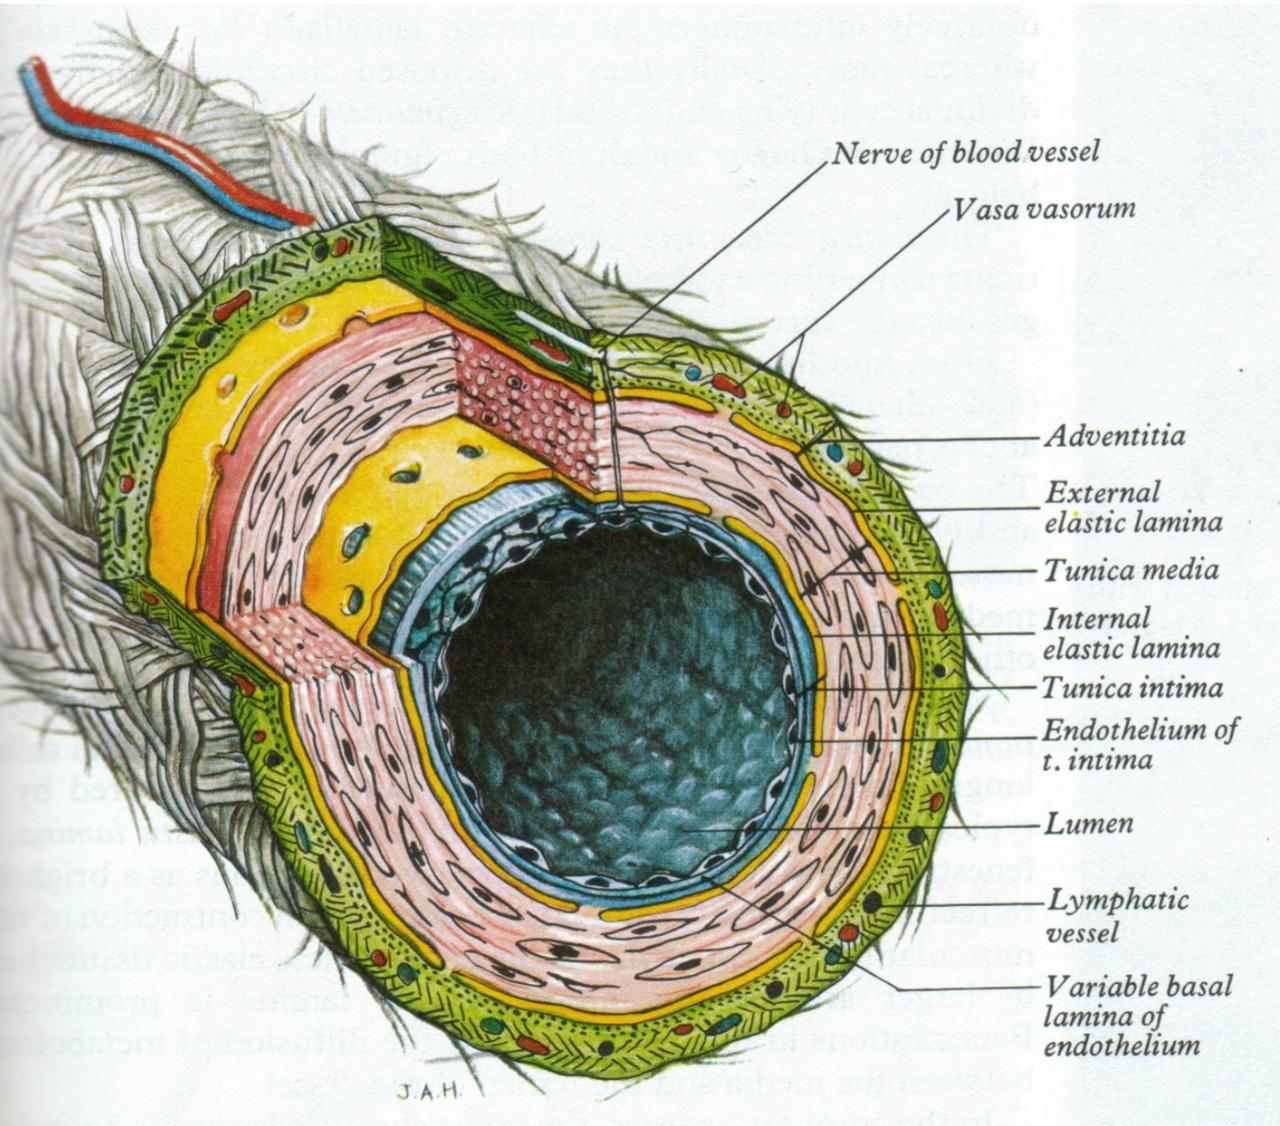

Fig 3.43: Opbouw van grotere bloedvaten

|

|